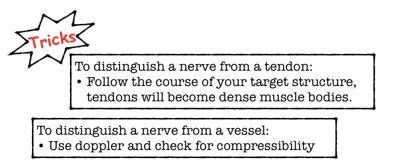

Difficulty clearly identifying nerves amongst the other structures is a common frustration. In cross-section on US, a nerve appears as an elliptical bundle containing many small scattered echogenic foci and running within a fascial plane. These blocks are best performed in the mid-forearm. The distal forearm has many tendons which may be mistaken for nerves and in the proximal forearm the nerves are deeper making them more difficult to target.